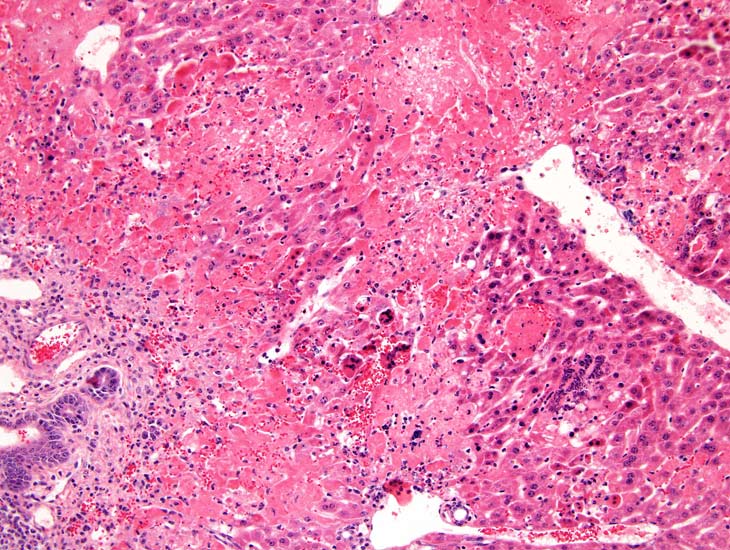

Extensive hepatic necrosis and inflammation in an athymic nude mouse with chronic mouse hepatitis virus (MHV) infection.

Mouse hepatitis virus infection in a SCID mouse. There is extensive hepatic necrosis.